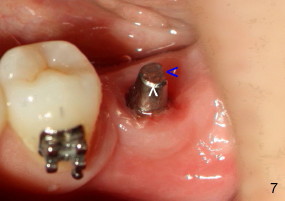

The tooth #19 has been lost for 8 years with tilting of #18 (black line in Fig.1). A 6x8 mm Bicon implant (3 mm post) was placed as distal as possible (I in Fig.2). Three months later, the implant was uncovered with evidence of osteointegration (arrowheads in Fig.3). A 4x6.5 mm 0 degree non-shouldered abutment with 3 mm post (A) was inserted into the implant well. The flat surface of the abutment needed to face distal in order to seat the abutment without interference. The implant/abutment complex was used as an anchorage to upright #18. The tooth #17 was extracted prior to orthodontic treatment (compare Fig.5,6 vs. 1-3). A bracket was bonded to Jet temporary crown of #19 and open coil spring was placed between #18 and 19. In the first two months, distalization of #18 is limited (between black and white lines in Fig.4), partially due to the fact that the bracket of #19 was debonded quite easily. A premolar band (B in Fig.5) was cemented to the temporary crown of #19. In another two months, the tooth #18 was pushed to desired position (arrowhead) under the tension of open coil spring (*). The mesial crest height of #18 was increased during uprighting (arrow, as compared to Fig.1-3). A new temporary crown was fabricated to fit the enlarged space of #19 with cementation of a molar band. The next problem is that the new molar temporary crown was easily dislodged from the 4x6.5 mm abutment even with a permanent cement. A larger abutment (5x6.5 mm) was used (Fig.6), with relining the temporary crown. The upper end of the larger abutment has sharp edge (Fig.8: white arrowhead, as compared to rounded edge of the smaller abutment (Fig.7). This may also contribute to better retention. In another 3 months, the temporary crown was dislodged again. An even larger abutment (6.5x6.5 mm with two flat surfaces (blue arrowheads in Fig.9) was adopted.